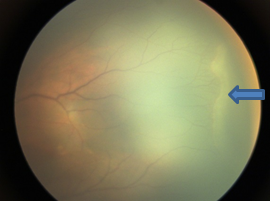

可疑家族性渗出性玻璃体视网膜病变